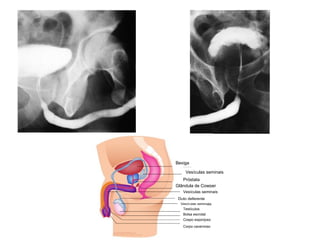

Sistema Reprodutor Ógãos que produzem, transportam e armazenam células germinativas Testículos  e ovários produzem células germinativas maduras.  Órgãos de transporte e armazenamento Homem: Ducto deferente,  próstata e  pênis Mulher: útero,  trompas uterinas e  vagina

Bexiga Vesículas seminais Próstata Glândula de Cowper Vesículas seminais Duto deferente Vesículas seminais Testículos Bolsa escrotal Cospo esponjoso Corpo cavernoso

Sistema Reprodutor Ógãosque produzem, transportam e armazenam células germinativas Testículos e ovários produzem células germinativas maduras. Órgãos de transporte e armazenamento Homem: Ducto deferente, próstata e pênis Mulher: útero, trompas uterinas e vagina

Bexiga Vesículas seminaisPróstata Glândula de Cowper Vesículas seminais Duto deferente Vesículas seminais Testículos Bolsa escrotal Cospo esponjoso Corpo cavernoso